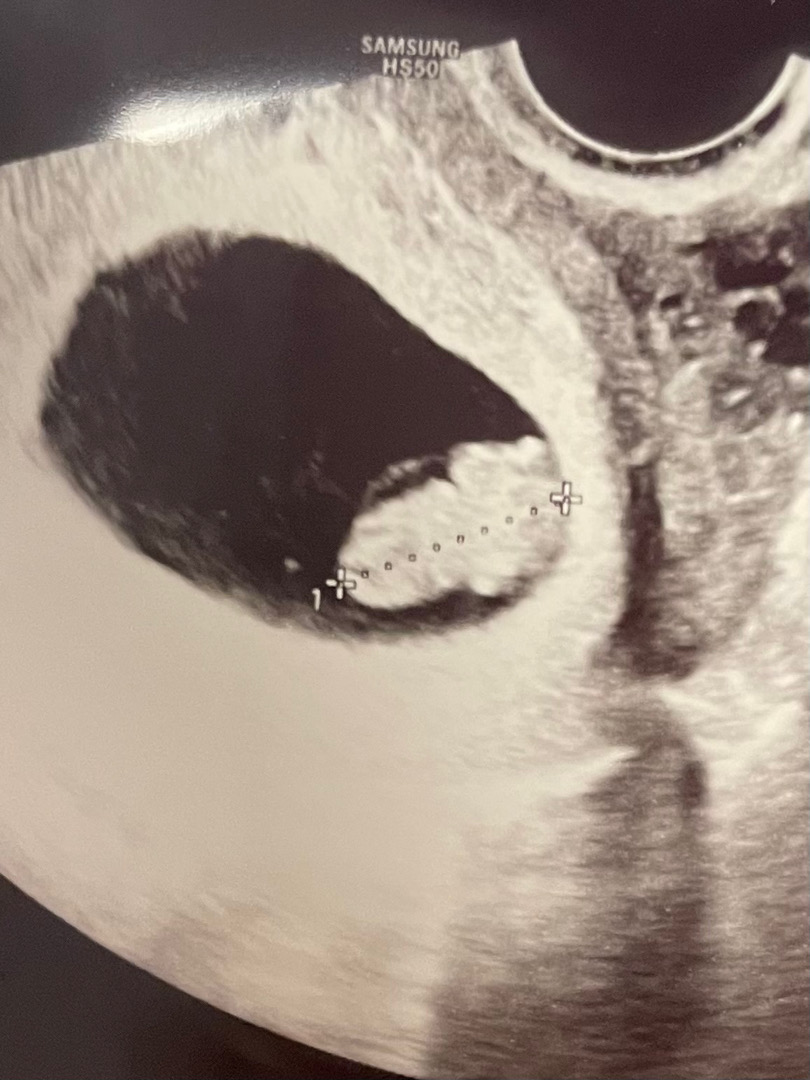

8주1일차 통닭

다들 8주차에 곰젤리 볼 수 있다고 해서 내심 기대했는데 사촌언니가 보자마자 “통닭같다” 하더라구요ㅋㅋㅋㅋㅋ 근데 그 말 들으니 진짜 통닭같고 하필 어제 옛날통닭을 먹어서 혼자 한참을 웃었네요ㅎㅎ 의사 선생님께서는 애기집도 넓고 건강하다고 한달 뒤에 오라던데...한달 뒤에는 성별을 알 수 있겠지요?